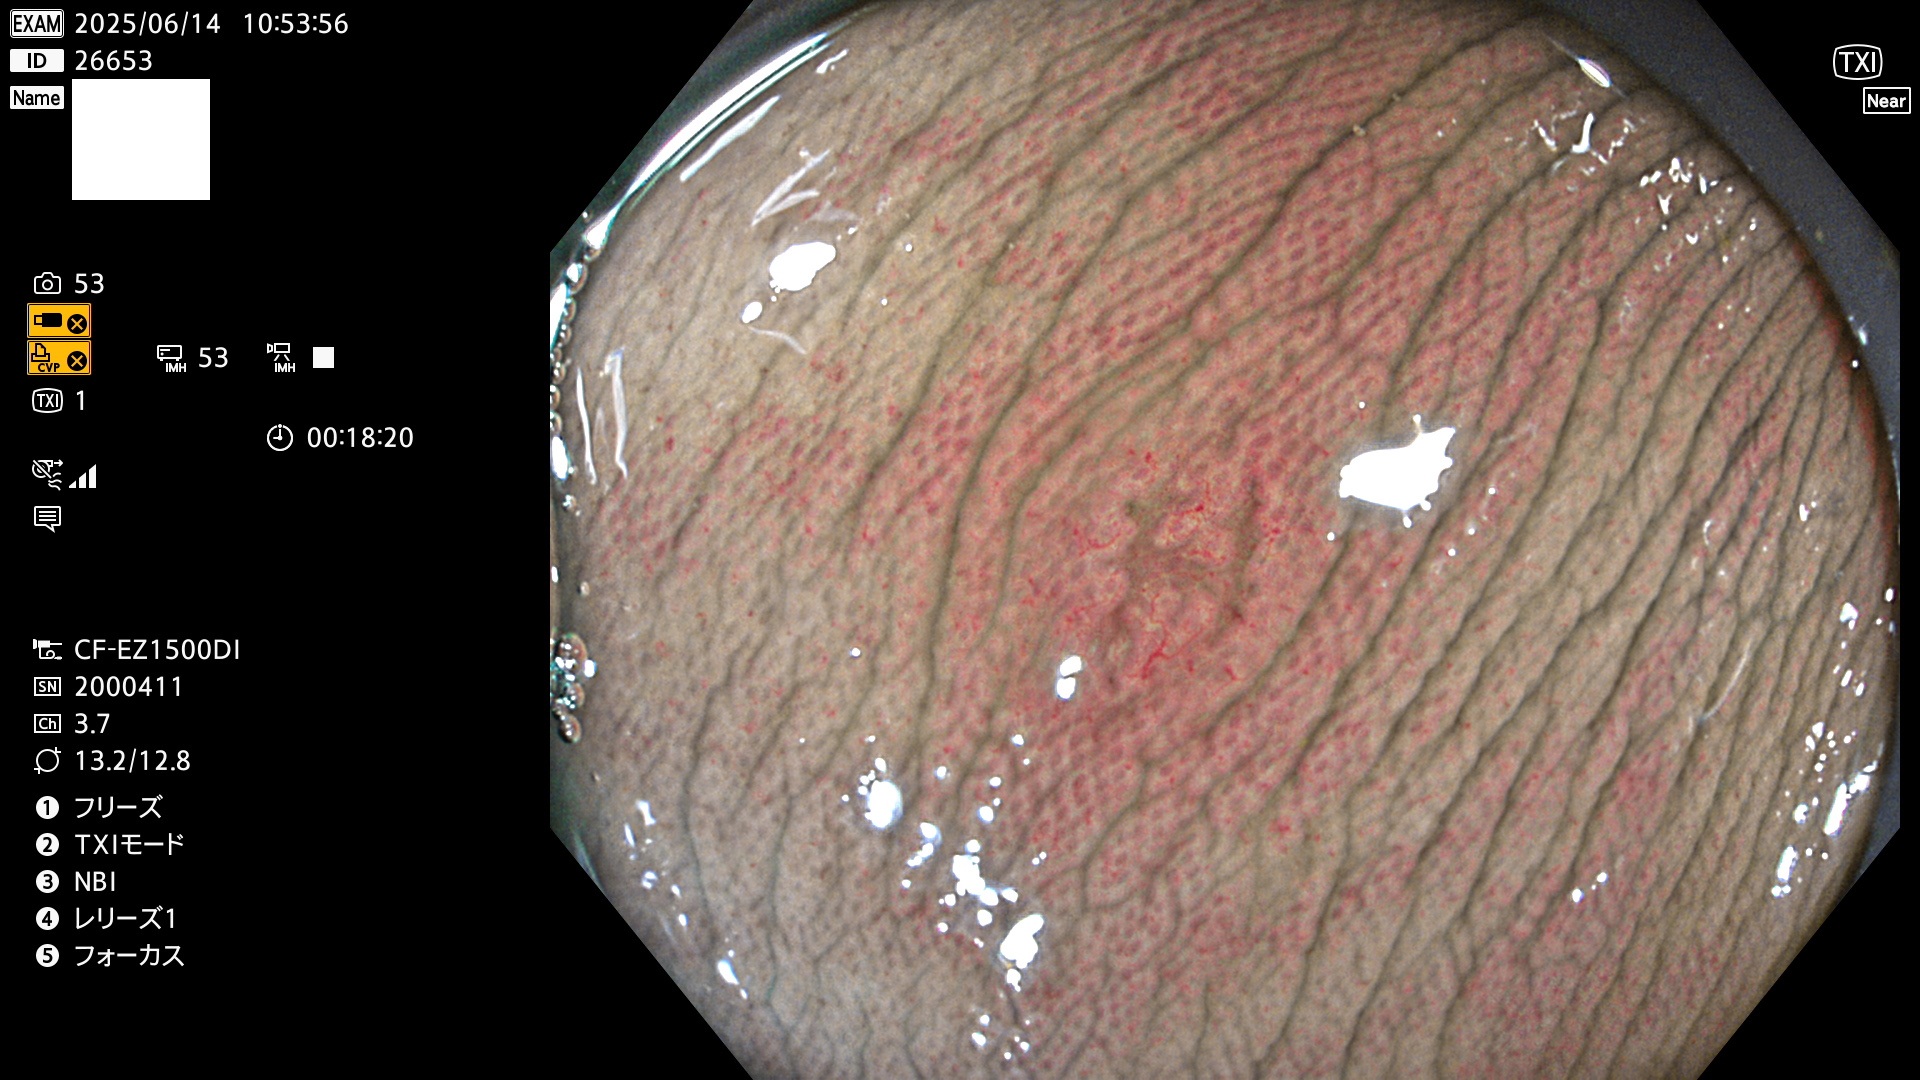

完全に平坦な物をUb、陥凹している物をUcと呼びます。Ubは認識が困難で、Ucはびらん(炎症)と紛らわしいために見落とされやすく、「内視鏡後・大腸癌」の原因になります。

抽出の対象期間 2025年6月12日〜6月15日の4日間(48件の検査)14個 (14/48=29%)